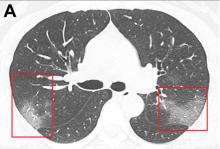

January 31, 2020 — One of the first imaging studies on the coronavirus (2019-nCoV) was published online today as radiologists scramble to find out how the virus presents in medical imaging. In just 30 days after the virus first appeared in China, it has spread to more than 8,200 confirmed cases and more than 170 deaths. Cases are now being reported in several countries, including the United States and Canada.